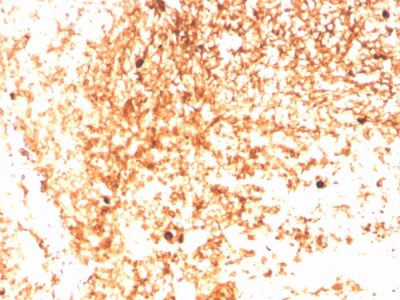

识别 75 kDa 的蛋白质,被鉴定为人类免疫球蛋白的 mu 重链。它不与 α (IgA)、γ (IgG)、ε (IgE) 或 δ (IgD)、重链、T 细胞、单核细胞、粒细胞或红细胞发生交叉反应。单体 IgM 在 B 细胞表面以膜结合抗体的形式表达,当由浆细胞分泌时以五聚体形式表达。IgM 抗体在对大多数抗原的早期免疫反应中表现突出。异常水平与免疫缺陷状态、遗传缺陷、骨髓瘤、华氏巨球蛋白血症、慢性感染和肝细胞疾病有关。该 MAb 可用于鉴定白血病、浆细胞瘤和某些非霍奇金淋巴瘤。这些恶性肿瘤最常见的特征是单一重链类的表达受限。